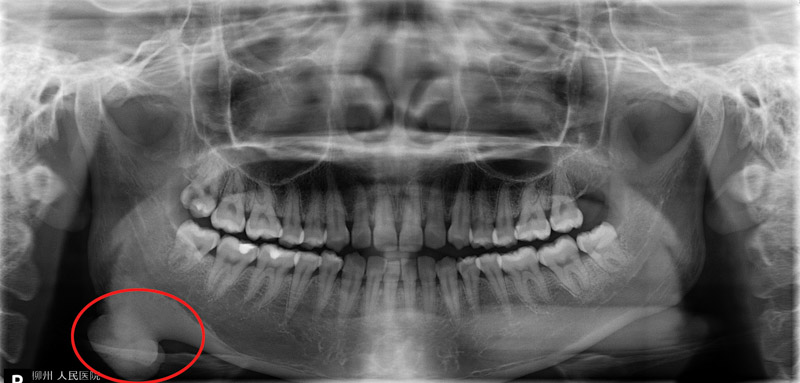

口腔科副主任醫(yī)師劉彥杰為唐女士做了仔細(xì)檢查,發(fā)現(xiàn)不是唐女士的臉越長越“方”,而是一顆骨性瘤子在作怪,這顆骨瘤正好就長在右側(cè)下頜角的位置。

下頜角截骨術(shù)(MAO)是一種對(duì)下頜角區(qū)進(jìn)行整形的手術(shù),主要適用于下頜角肥大的患者,手術(shù)從口內(nèi)做切口,用長柄擺動(dòng)鋸在十分狹小的視野中將下頜角截除整形,多用于改善臉型,該類手術(shù)在柳州市開展尚屬首次。